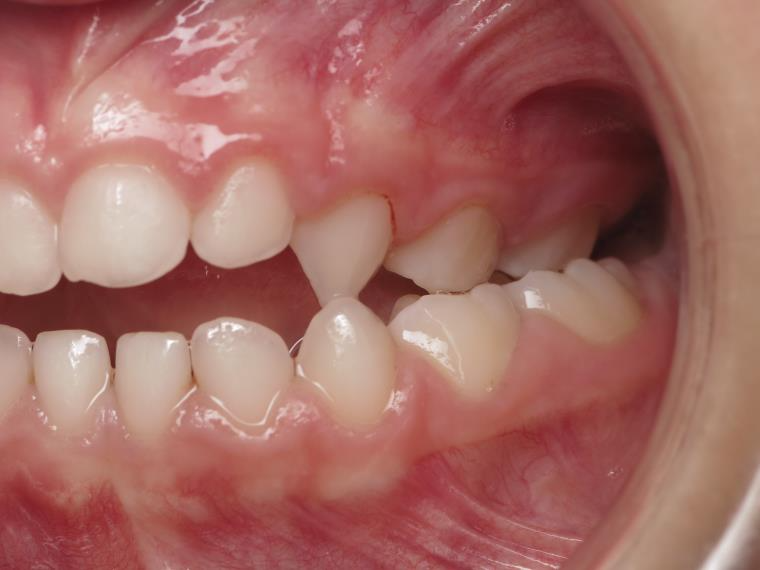

inversion postérieur coté droit et espace entre l'arcade du haut et du bas (béance)

bilan début et en cours de traitement